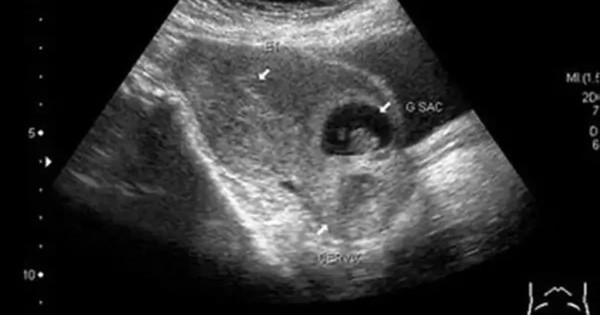

Một phụ nữ 40 tuổi tại Lạng Sơn suýt tử vong do tự ý phá thai khi mang thai tại vết mổ lấy thai cũ - bệnh lý hiếm gặp, nguy cơ băng huyết và sốc mất máu rất cao.